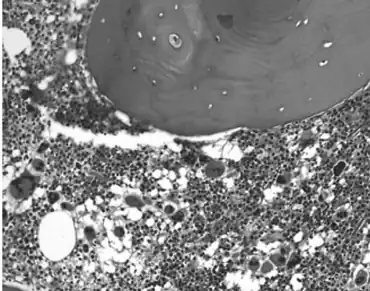

High number of megakaryocytes with atypical forms, consistent with the diagnosis of essential thrombocythemia